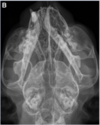

“Maxillofacial injuries and diseases that cause an open mouth in cats”. Constantaras & Charlier. JVD 2014. which side has coronoid impingement laterally? Note it on the radiograph.

LEFT Photograph (A) of a Persian cat with open-mouth jaw locking secondary to impingement of the coronoid process on the zygomatic arch. The dorsoventral radiograph (B) taken during the open-mouth jaw locking episode shows impingement of the left coronoid process with the zygomatic arch. Note the rotation of the mandibles to the left.